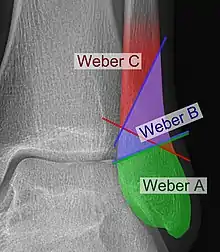

Danis–Weber classification on X-ray.

The Danis–Weber classification (often known just as the Weber classification) is a method of describing ankle fractures. It has three categories:[1]

Type A

Type B

Type C

Categories B and C imply a degree of damage to the syndesmosis itself (which cannot be directly visualised on X-ray). They are inherently unstable and are more likely to require operative repair to achieve a good outcome. Type A fractures are usually stable and can be managed with simple measures, such as a plaster of paris cast.